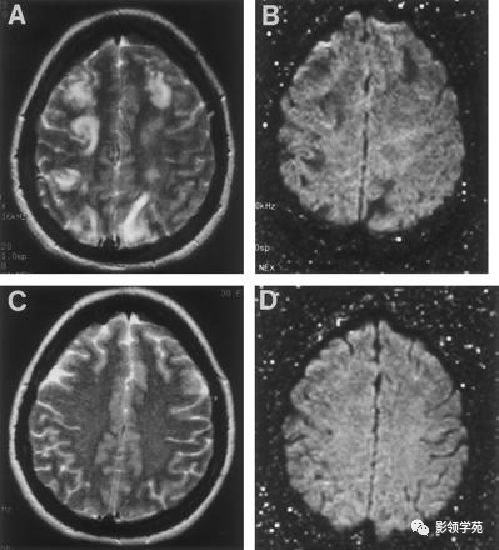

半数以上的患者为酒精中毒晚期,也可见于慢性消耗性疾病基础上出现营养不良和电解质紊乱。 低钠血症时脑组织处于低渗状态,过快补充高渗盐水使血浆渗透压迅速提高,引起脑组织脱水和血脑屏障破坏,有害物质透过血脑屏障可导致髓鞘脱失 。

头颅MRI 及CT 阴性仍不能完全排除CPM 诊断 。 由于CPM的典型病灶多在病后10 d 左右才出现,检查太早,脱髓鞘的病变尚未完全形成 。 过晚检查,病灶已自我修复,MRI 阳性率明显降低 。 单凭影像仍有误诊可能。